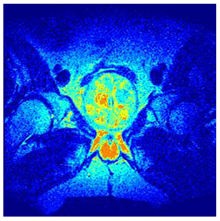

In this subsection, we will discuss the experiment designed to evaluate the performance of EO with cross-entropy for the segmentation of prostate MRI images. To this end, we use a group of reference images formed by a set of six prostate MRI images; see Figure 4. All the images from the group were extracted from the Ferenc Jolesz National Center for Image-Guided Therapy, Harvard Medical School, or Brigham Health Hospital datasets with no additional preprocessing [50]. Prostate MRI images are primarily used for disease diagnosis or to establish treatment for prostate-related diseases such as prostatitis, benign prostatic hyperplasia (BPH), and prostate cancer, among other diseases or medical conditions. In the context of this article, the images were used to test the efficiency of the equilibrium optimizing algorithm and compare it with the other six chosen algorithms. The segmentation of MRIs is carried out over four different thresholds levels: = 3, 4, 5, and 8. Due to the nature of the images, there was a limited number of different tissues in the images; thus, there was no point in evaluating a larger number of .

Figure 4.

Eleven transaxial-cut prostate MRI images. This figure presents a set of eleven transaxial-cut magnetic resonance (MR) images of the prostate. These images serve as the input dataset for evaluating the segmentation performance of the proposed algorithm.

Table 5 presents the segmentation of the MRIs using EO for a qualitative inspection. From Figure 5, it is clear that two lumps in the prostate have been highlighted by the thresholding process. Prostatic MRIs present noisy conditions, which makes it difficult to visualize the thresholding with the naked eye, so in Figure 5 we present the thresholded image as well as the histogram with the values of the thresholds generated by the EO. It can be observed in the histogram that the thresholds present an adequate distribution, even though this particular image has impulsive noise and a simple shape. Our findings indicate that four thresholds are typically sufficient for this application, which corresponds to identifying five different tissue types in the image. A smaller threshold value may result in a lack of sufficient contrast to highlight relevant anatomical structures, such as the prostate capsule. In contrast, a higher number of thresholds may lead to the incorrect differentiation of anatomical regions that should be connected.

Table 5.

Segmentation of transaxial-cut prostate MRI images Using EO and cross-entropy. This table presents the segmentation results of transaxial-cut prostate MRI images using the equilibrium optimizer (EO) and cross-entropy. Each row corresponds to a distinct MRI image, while the columns nt represent the number of thresholds applied during segmentation. The results illustrate the performance of the EO algorithm across different threshold levels for each image.